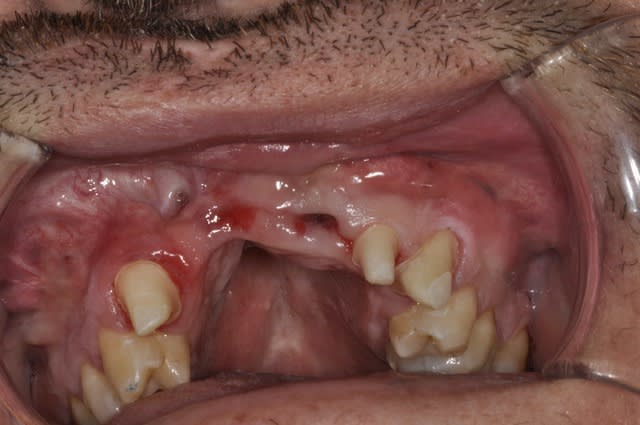

Bridge sur patient ayant une fente faciale.

J'ai du déposé le bridge ailette et faire l'extraction de 11 et 21 pour cause resorption externe.

Puis bridge sur dent vivante avec 13/22/23 comme pilier.